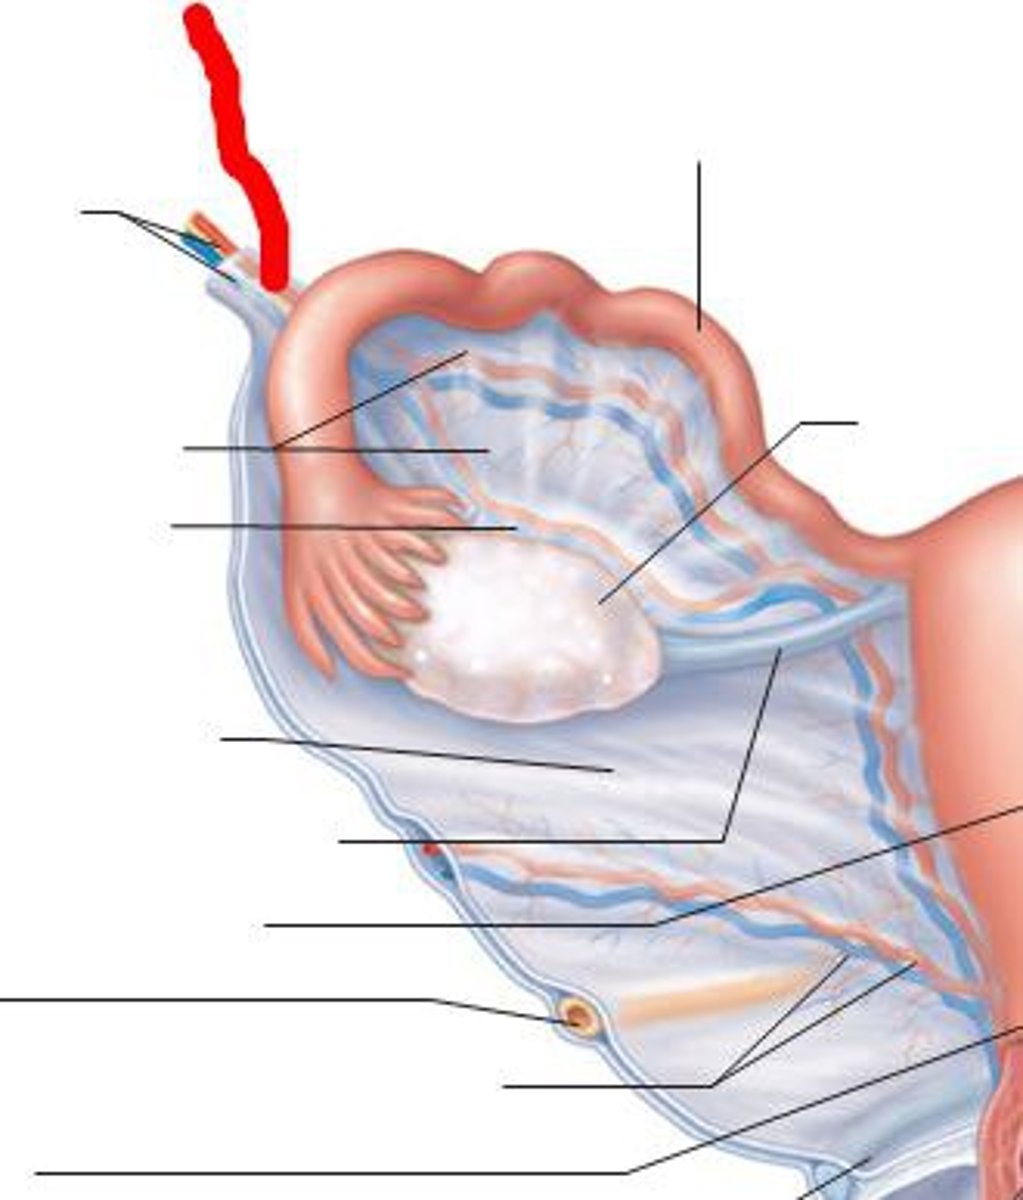

outer cortex

What layer of the ovary houses the developing gametes, called OOCYTES that are within FOLLICLES?

inner medulla

What layer of the ovary is comprised of loose connective tissue containing the MAIN OVARIAN BLOOD VESSEL, LYMPH VESSELS, and NERVES?

premordial follicles

The ovaries of a newborn female contain many thousands of ____________, each of which consists of an oocyte surrounded by a layer of flat follicular cells

Follicular phase, ovulation phase and luteal phase

The ovarian cycle has 3 phases:

Oogenesis

the production of the female gametes (ova)

primary oocyte

stay in meiosis I until ovulation occurs years later

secondary oocyte

stays in meiosis II until a sperm penetrates it

fimbriae

Fingerlike projection of the uterin (fallopian) tubes that drape over the ovary.